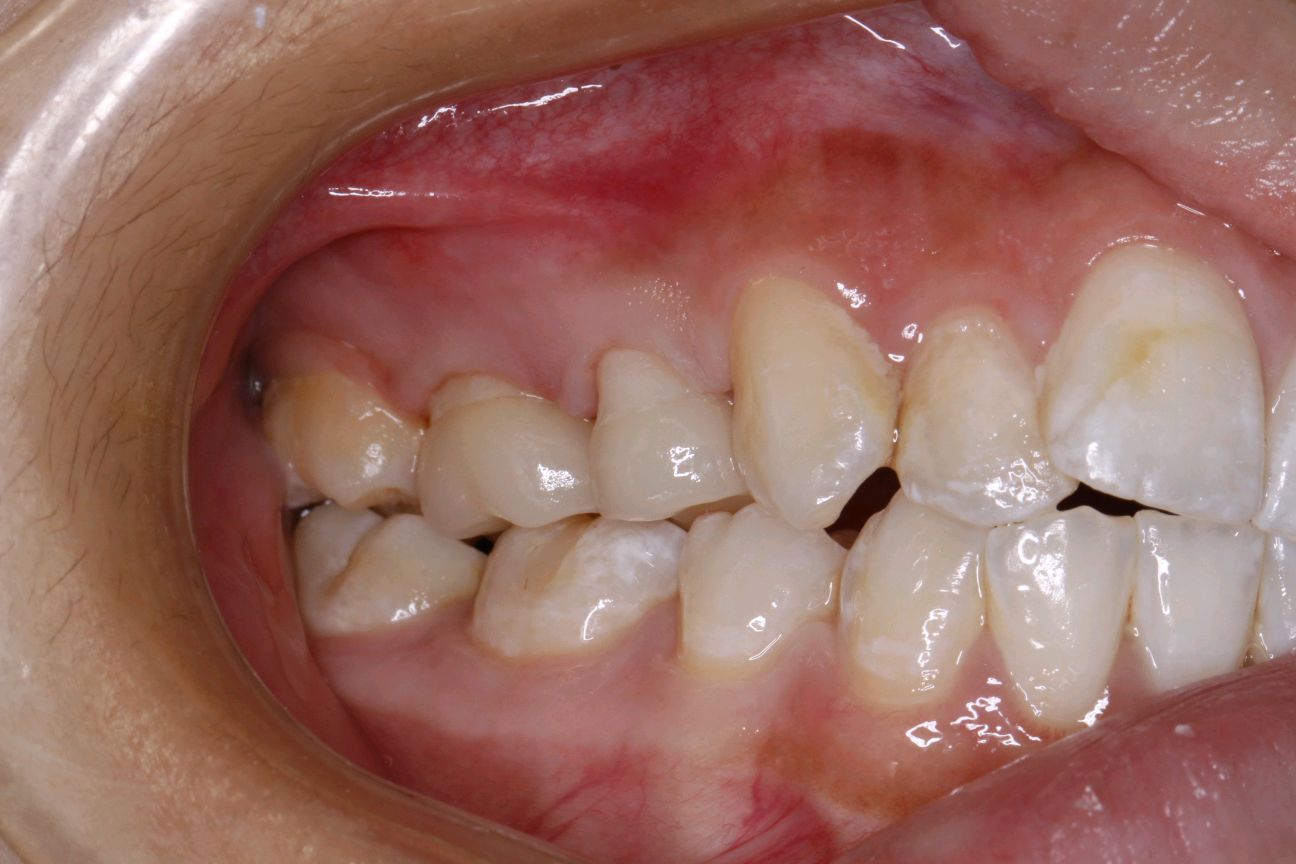

嵌体是一种少磨牙、能较好恢复咬合关系和邻接关系的有效修复方式;但同时也是一项技术要求较高的修复方式,尤其在牙体预备和粘接流程和细节的把控上难度很大,因此要求医生有较高的专业技术!